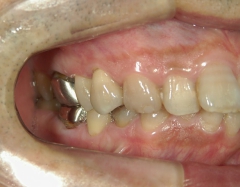

no.22_8175_治療前_右.jpgno.22_8175_治療前_正面.jpgno.22_8175_治療前_左.jpg

矯正歯科 治療後 左上6番欠損のため、7番を6番の位置へ前方牽引

no.22_8175_治療後_右.jpgno.22_8175_治療後_正面.jpgno.22_8175_治療後_左.jpg